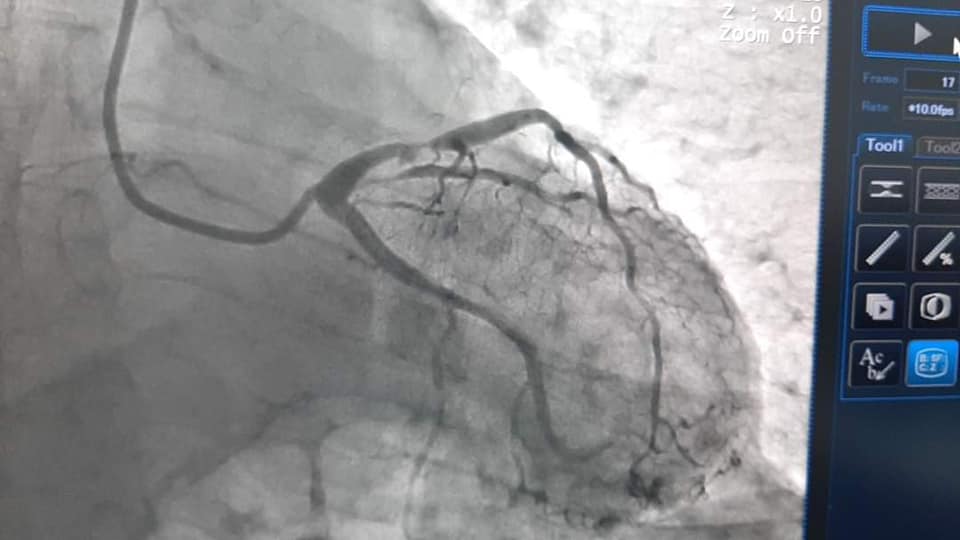

Пацієнт Нецюк А.М. поступив до лікарні з симптомами нестабільної стенокардії та був скерований кардіологами на коронарографію.

“В лівій коронарній артерії у пацієнта було виявлено атеросклеротичну бляшку з критичним звуженням, яка могла привести до розвитку інфаркту міокарду. Перед звуженням відмічалося невелике розширення, яке могло бути як тромбованою додатковою гілкою коронарної судини, так і розірваною атеросклеротичною бляшкою. Оптична когерентна томографія дозволила визначити що має місце саме розрив бляшки, що загрожує великим інфарктом. На це місце було імплантовано стент та виконано контроль якості прилягання стента до стінки судини. ОКТ показала відмінний результат стентування”, – зазначає завідувач відділенням інтервенційної радіології, кардіології та реперфузійної терапії, лікар-хірург серцево-судинний Богдан Маслій.